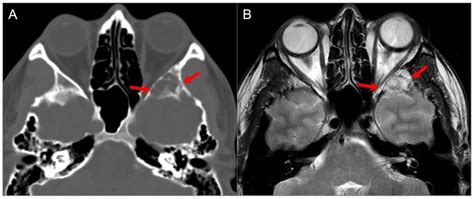

To confirm the presence of a tumor, specialists typically employ a variety of advanced imaging techniques. A standard physical examination is often followed by specialized diagnostic tests to map the extent of the tumor:

MRI (Magnetic Resonance Imaging) Provides high-resolution images of soft tissues, nerves, and the brain.

CT Scan (Computed Tomography) Highly effective at highlighting bony structures and identifying tumor-related bone erosion.